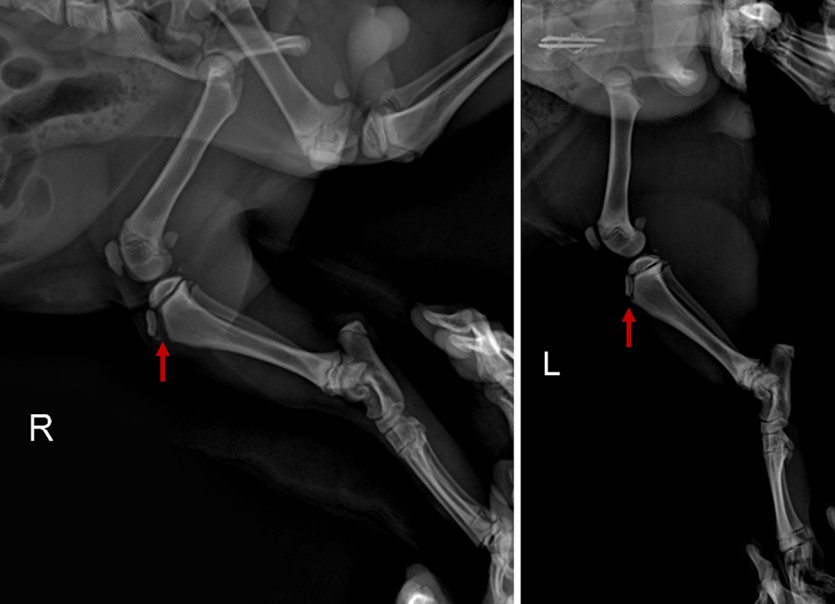

<수술 전 방사선 사진 : 좌측의 정상적인 경골조면(우측 사진 화살표)과 다르게 떨어져 나간 우측 경골조면(좌측 사진 화살표)이 확인된다>

방사선 촬영 결과, 우측 경골 조면의 박리 골절 (Tibia tuberosity avulsion fracture) 이 확인되었습니다.

경골조면에 부착하는 인대가 과도하게 잡아당겨지면서 골편이 위쪽으로 분리된 상황입니다. 골편의 이동이 큰 경우 당겨지는 힘, 견인력이 작용하기 때문에 외과적으로 수술을 해 주는 것이 필수적입니다.

특히 신체에서 가장 큰 근육 다발인 대퇴사두근의 부착부인 경골 조면의 박리 골절의 경우 아이들 체중의 몇 배의 견인력이 작용하기 때문에 반드시 수술적 교정 및 고정이 필요하며, 골절부가 완전히 안정화 될 때까지 운동제한도 필수입니다.

다 자란 성묘보다는 아직 성장판이 덜 닫힌 어린 고양이나 강아지에게서 주로 나타나며 높은 곳에서 점프를 하거나 아래로 뚝 떨어지는 것과 같은 충격에 의해 발생하는 경우가 많습니다.